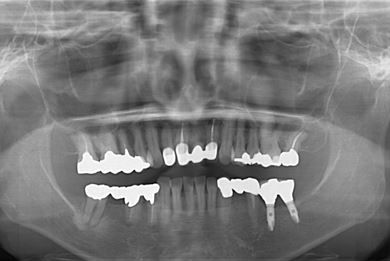

インプラントの症例写真 IMPLANT

インプラント治療+セラミック治療

| 治療内容 | インプラント2本、オールセラミック4本(ジルコニアフレーム、オールセラミック用の土台1本) | ||||||||||||||||||||||||||||||||

| 総治療費 | 1,299,000円 | ||||||||||||||||||||||||||||||||

| 治療期間 | 7ヶ月 |